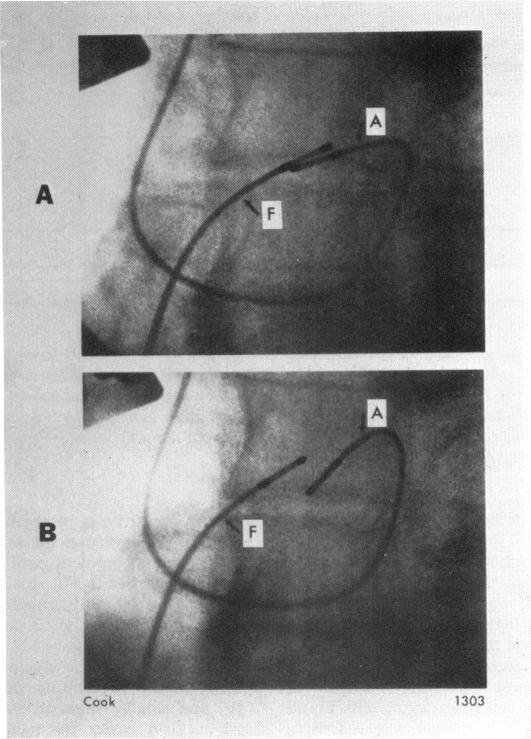

A new catheter technique for His bundle recordings via the arm veins.

Br Heart J. 1973 Dec;35(12):1226-33. doi: 10.1136/hrt.35.12.1226.